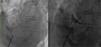

Subsequently, the patient underwent percutaneous closure of the PFO with a 25 mm Amplatzer® cribriform occluder device (Figure 4). The procedure was uneventful, with no evidence of residual right-to-left shunt at the final angiogram. Clinical follow-up has been favorable, with the patient free from breathlessness and desaturation episodes, thus enabling a full functional recovery from hip surgery.